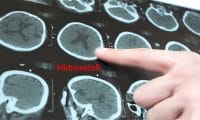

Bu sıvıya beyin omurilik sıvısı bel suyu bos denmektedir. Beyin kaynaklı hastalıkların en önemlisi menenjit hastalığı teşhis edilmesi gibi durumlarda bu beyin omurilik sıvısı örneği gerekebilir. Beyin omurilik sıvısı yani bel suyu kapalı bir sistemi ifade eder. Hidrosefali aşırı beyin omurilik sıvısının bos beyindeki boşluklarda birikmesi ve kafa içindeki basıncı artırması durumudur beyin omurilik sıvısı beyinde ve omurilikte üretilerek beyni dış etkilerden korumaya yardımcı olur.